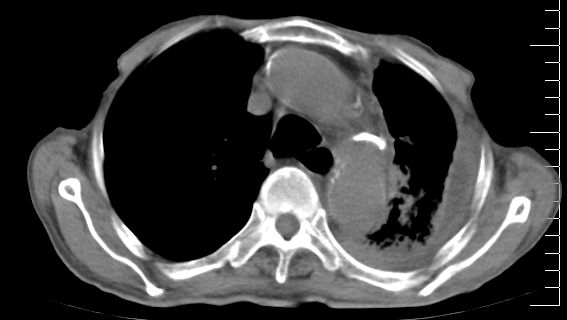

标题: CT10141:男、84岁,咳嗽、咯血1年。 [打印本页]

标题: CT10141:男、84岁,咳嗽、咯血1年。

1左侧胸腔积液并包裹2心包积液3左下肺癌?建议支纤镜检。

支持左侧中央型肺癌伴下叶肺不张\\纵隔淋巴结转移.左侧包裹性胸腔积液\\心包积液.左侧少量胸腔积液..慢性支气管炎伴部分间质纤维化.

支持:左侧中央型肺癌伴下叶肺不张\\纵隔淋巴结转移.左侧包裹性胸腔积液\\心包积液.左侧少量胸腔积液..慢性支气管炎伴部分间质纤维化.另:支气管分支根部明显阻塞 狭窄,内膜凸凹不平,提示内膜增生物。

左肺中心性肺癌并肺不张,同侧 胸膜及心包转移,左肺癌性淋巴管炎

左侧中心型肺癌,左侧胸腔积液部分包裹,心包积液,肿膈淋巴结显示。

左侧中央型肺癌伴下叶肺不张\\纵隔淋巴结转移.左侧包裹性胸腔积液\\心包积液.左侧少量胸腔积液..慢性支气管炎伴部分间质纤维化

咯血病史较长,左肺下叶实变,体积未明显缩小,隐约可见血管影及坏死阴影,双肺门及纵隔淋巴结增大,心包增厚积液,纵隔右移位,单侧胸腔积液,首先考虑:大叶型肺泡癌伴纵隔心包转移。

左下中央型肺癌伴阻塞性不张,肺炎,左侧包裹性胸腔积液\\心包积液

左肺中心性肺癌并左肺下叶肺不张,纵隔淋巴转移、同侧胸腔及心包积液(转移)。